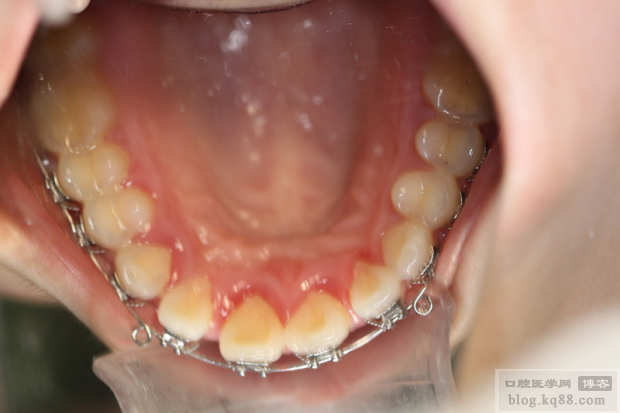

- 原因: 这是最常见的问题,矫治器(托槽、弓丝、带环等)会显著增加口腔清洁的难度,容易在牙齿表面、托槽周围、牙龈边缘堆积食物残渣和菌斑,如果患者不能有效清洁,细菌会刺激牙龈导致牙龈炎(红肿、出血),如果炎症持续进展,破坏牙周韧带和牙槽骨,就会发展为牙周炎(牙龈退缩、牙周袋形成、牙槽骨吸收、牙齿松动)。

- 风险因素: 患者口腔卫生习惯差、本身有牙周病史、矫治器设计复杂(如舌侧矫治器)、矫治器本身有刺激性边缘。